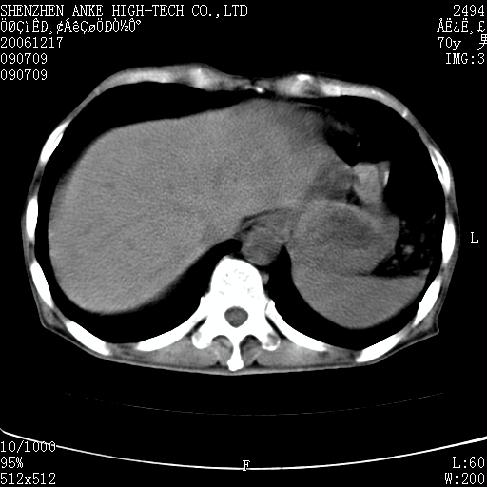

患者:男,70岁,腹部疼痛待查.b超见左肾脏占位待排.因为患者经济条件不好,没有做增强.

支持胰腺癌伴肝转移;左肾囊肿?

胰尾与左肾上缘部位见有一肿块影,密度不均匀,周围边界不清晰,与胰腺相连,与左肾边界不清,肝脏内见有多发低密度影,考虑胰尾癌伴左肾侵犯并肝内转移。最好是做个增强。

考虑:1,胰腺癌伴肝转移;2,左肾小囊肿。

与胃、脾及左肾之间见一巨大肿块影,其内密度不均,边界欠清,与胰腺关系密切。肝实质内见多个类圆形低密度灶,边界较清。符合胰腺癌并肝转移表现。

考虑:1,胰腺癌伴肝转移;2,左肾小囊肿. 3胰腺病变与左肾分界不清,肾脏可能受累。

与胃、脾及左肾之间见一巨大肿块影,其内密度不均,边界欠清,与胰腺关系密切。肝实质内见多个类圆形低密度灶,边界较清。符合胰腺癌并肝转移表现。

同意胰尾部癌累及左肾前,肝多发转移,左肾小囊肿。

胰尾与左肾上缘部位见有一肿块影,密度不均匀,周围边界不清晰,与胰腺相连,与左肾边界不清,肝脏内见有多发低密度影,考虑胰尾癌伴左肾侵犯并肝内转移。最好是做个增强。